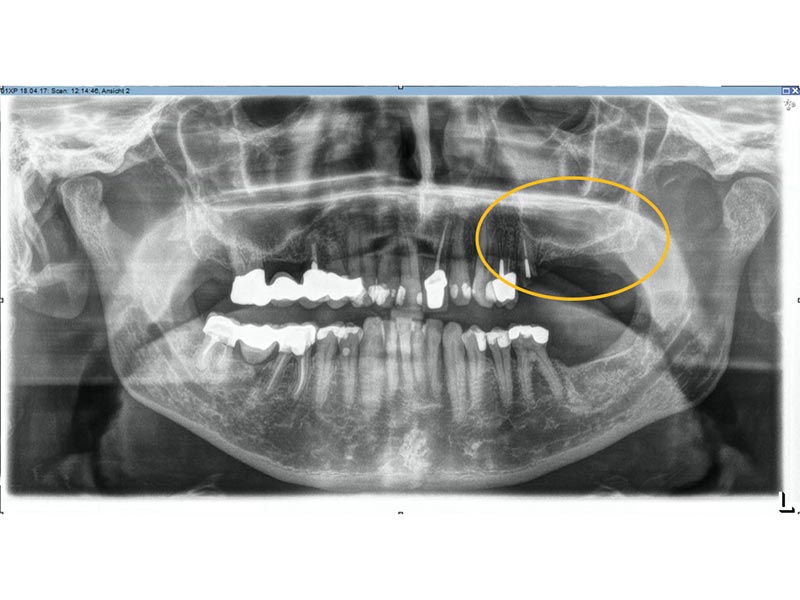

Unter dentalen Implantaten versteht man im allgemeinen eine Schraube, die dort, wo ein oder mehrere Zähne verloren gegangen sind, in den Kieferknochen "eingepflanzt" wird. Diese Therapieform der Implantologie hat sich in den letzten Jahren zu einem alltäglichen Therapieverfahren in der Zahnheilkunde entwickelt. Wissenschaftliche Untersuchungen zeigen hierfür eine Erfolgsquote von i. d. R. 80-98 % über 10 Jahre. Verglichen mit anderen zahnärztlichen Maßnahmen gibt es nahezu keine andere Therapie mit derart guten Erfolgsaussichten. Auch eine Verbesserung der Lebensqualität wird durch implantatgetragenen Zahnersatz laut klinischer Studien erreicht.

Mittlerweile hat sich die Implantologie zu einem alltäglichen Therapieverfahren mit sehr guten Erfolgsaussichten in der Zahnheilkunde entwickelt. Bei guter Mundhygiene und regelmäßigen Kontrolluntersuchungen können fachmännisch gesetzte Zahnimplantate ein Leben lang halten.